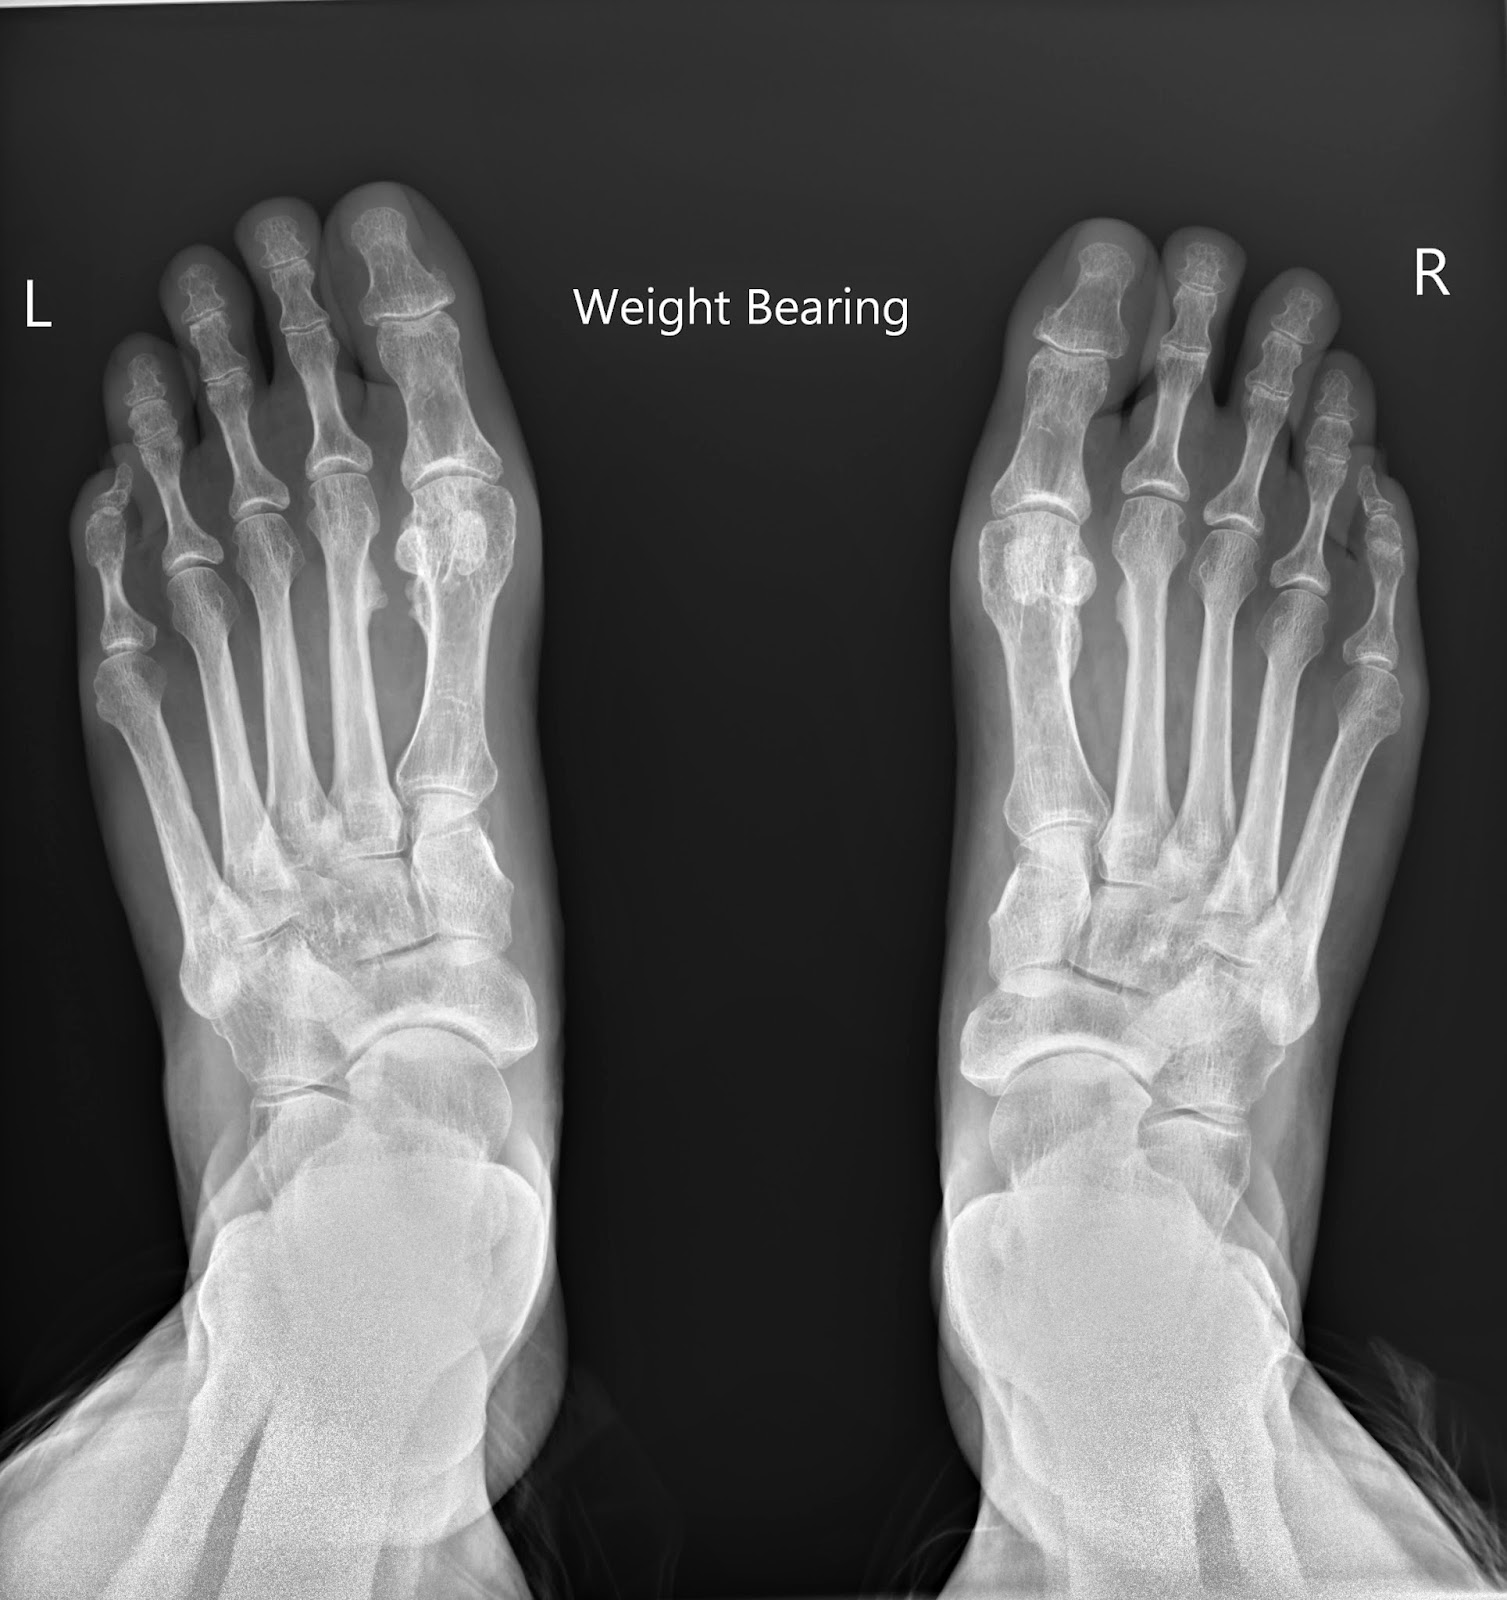

Bunions, Xray Stock Image C052/9381 Science Photo Library Do Bunions Show Up On Xrays Painful prominence at 5th metatarsal head laterally. In this video we will look at how to measure the angles on bunions and. They may be tender on. If they’re at the big toe, they’re just called bunions, dr. Abnormal 1st metatarsophalangeal angle and 1st. However, it behooves the surgeon to be aware of subtleties. Types of bunions are mainly organized. Do Bunions Show Up On Xrays.

Xray of bunions stock photo. Image of ache, health, bunion 4862118 Do Bunions Show Up On Xrays Abnormal 1st metatarsophalangeal angle and 1st. However, it behooves the surgeon to be aware of subtleties. They may be tender on. In general, specific laboratory studies are unnecessary. Painful prominence at 5th metatarsal head laterally. Types of bunions are mainly organized by where they are located and how bad they are. Healthy joints have a clear, even space between. If. Do Bunions Show Up On Xrays.

Xray of bunions on toes (image 1 of 2) Stock Image C003/1029 Do Bunions Show Up On Xrays Healthy joints have a clear, even space between. If they’re at the big toe, they’re just called bunions, dr. Abnormal 1st metatarsophalangeal angle and 1st. Bunionettes are visible on clinical examination as an erythematous swelling overlying the 5 th metatarsal head. In general, specific laboratory studies are unnecessary. Painful prominence at 5th metatarsal head laterally. Types of bunions are mainly. Do Bunions Show Up On Xrays.

Bunions, Xray Stock Image C023/9740 Science Photo Library Do Bunions Show Up On Xrays If they’re at the big toe, they’re just called bunions, dr. Healthy joints have a clear, even space between. Abnormal 1st metatarsophalangeal angle and 1st. In this video we will look at how to measure the angles on bunions and. They may be tender on. Bunionettes are visible on clinical examination as an erythematous swelling overlying the 5 th metatarsal. Do Bunions Show Up On Xrays.

Bunions, Xray Stock Image C052/9576 Science Photo Library Do Bunions Show Up On Xrays However, it behooves the surgeon to be aware of subtleties. They may be tender on. If they’re at the big toe, they’re just called bunions, dr. In general, specific laboratory studies are unnecessary. Painful prominence at 5th metatarsal head laterally. Bunionettes are visible on clinical examination as an erythematous swelling overlying the 5 th metatarsal head. In this video we. Do Bunions Show Up On Xrays.